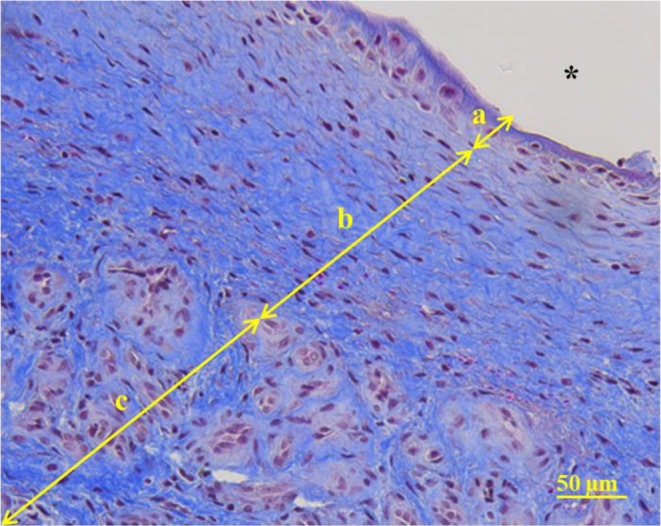

The reconstruction of large bone defects remains challenging for orthopedic surgeons. Autologous bone grafts (ABGs) are the gold standard treatment for limited size defects, but larger bone defects (> 5 cm) require the use of more sophisticated techniques, such as the Masquelet technique. Over the last three decades, the Masquelet or induced membrane technique (IMT) has become increasingly popular as it does not require high-precision microsurgery skills and the time taken to achieve bone consolidation is independent of the length of the defect. IMT is a two-stage procedure. In the first stage, a polymethylmethacrylate (PMMA) cement spacer is implanted into the bone lesion and a physiological immune reaction initiates the formation of a fibrotic induced membrane (IM) with both angiogenic and osteogenic properties. The second stage, performed several weeks later, involves removal of the spacer followed by the implantation of a standard ABG in the preserved IM cavity for subsequent bone repair. In this extensive review, we explain how the success of this surgical procedure can be attributed to the synergy of four key components: the inducer (the PMMA cement), the recipient (the IM), the effector (the bone graft) and the modulator (the mechanical environment). Conversely, we then explain how each key component can contribute to the failure of such treatment. Finally, we discuss existing or emerging innovative and biotechnology-oriented strategies for optimizing surgical outcome with respect to the four components of IMT described above.